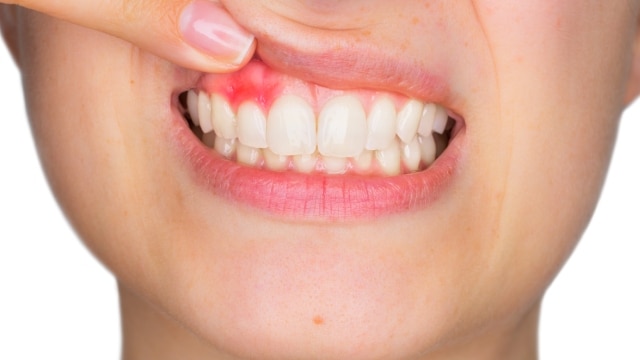

Vamos falar sério sobre gengiva. Você sabia que sangrar ao escovar os dentes ou usar fio dental não é normal? Pois é, muita gente ignora, mas esse é um dos primeiros sinais de que algo não vai bem. A gengivite, que começa com um simples incômodo, pode evoluir e virar um problemão se não cuidarmos. Se a sua gengiva anda machucando, fique atenta!

Quando a gengivite se agrava, ela pode causar o que chamamos de “gengivite expulsiva”. Isso significa que a gengiva começa a se afastar dos dentes, criando espaços onde sujeira e bactérias se acumulam ainda mais. Imagina só, os dentes parecem mais longos e até a sensibilidade pode aumentar. É um sinal claro de que a saúde bucal precisa de atenção urgente.

Quando a gengiva começa a mostrar sinais de que não está feliz – um inchaço leve, um vermelho que não some – é hora de agir. Ignorar pode piorar a situação. Lembre-se que a saúde bucal reflete a saúde geral do corpo. Cuidar bem da sua gengiva é um investimento em você.